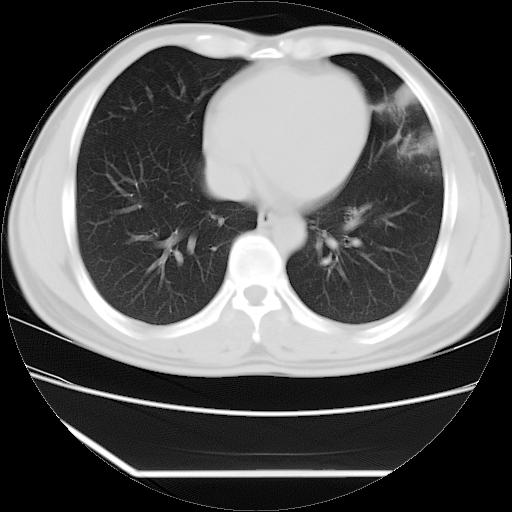

男,38岁,于2009年8月9日晚突发左侧胸痛,今x线提示左下肺阴影,为了明显确诊断,行ct检查,

血常规:嗜酸性细胞增高,单核细胞增高。

病灶发生在下叶,密度均匀,边缘模糊、毛糙,周围血管纹理增强扭曲改变,靠近胸膜处病灶胸膜反应明显。

支持考虑---球形肺炎。

左肺舌叶病变。主体病灶呈类圆形中心密度低,成液化趋势周边班片影分布

考虑肺脓肿

虽然实验室检查支持炎性病变,且病变内有坏死改变(中央呈大片状低密度影),但仍不能掉以轻心,鳞癌也可以有这种影像改变。